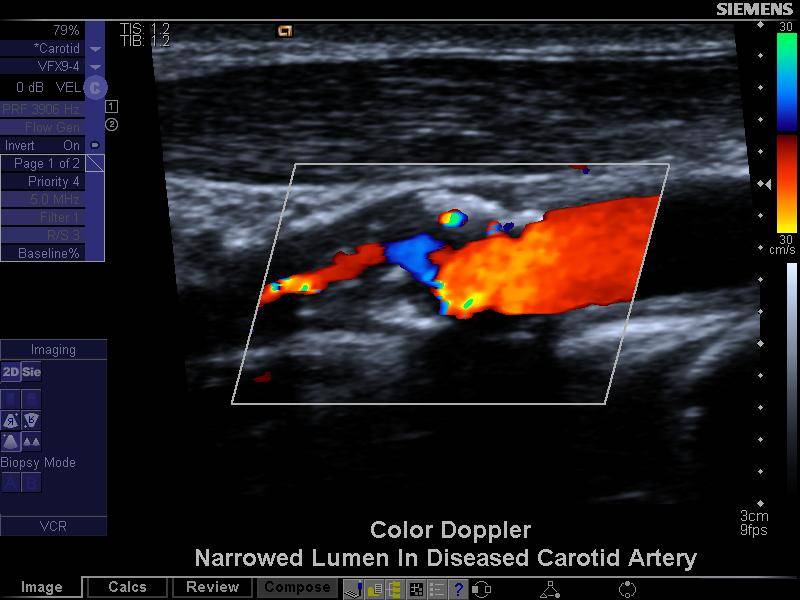

Farbduplex-Sonographie

Hochauflösende Bildgebung der Gefäßwände mit farbiger Darstellung der Blutströmung. Ermöglicht die genaue Beurteilung von Gefäßverengungen.